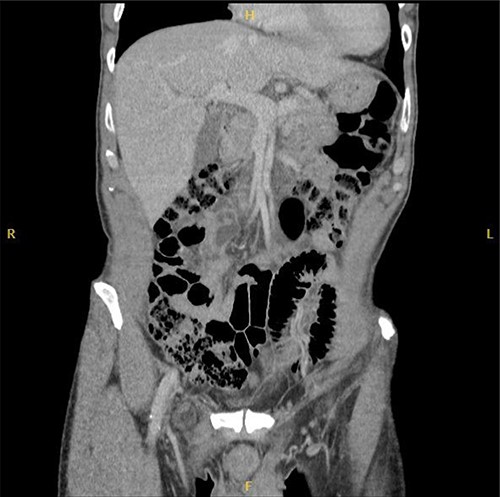

Computed tomography (CT) was reported as demonstrating an inguinal hernia containing fat and possibly the vermiform appendix (Figs 1 and 2). There was no conclusive evidence of appendicitis.

The patient was taken to theatre later that day for exploration via a modified McEvedy’s high approach. This demonstrated a hernia sac originating posterior to the inguinal ligament, emerging medial to the femoral vessels. A femoral hernia was diagnosed and exploration of the hernia sac demonstrating the vermiform appendix with necrosis of the distal segment. Appendicectomy was completed and primary suture repair used to repair the defect to the femoral canal.